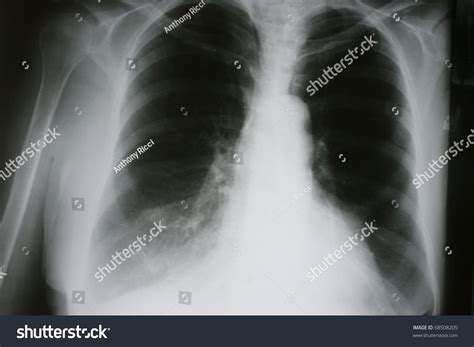

• Chest X-ray: An initial imaging test to detect any abnormalities in the lungs.